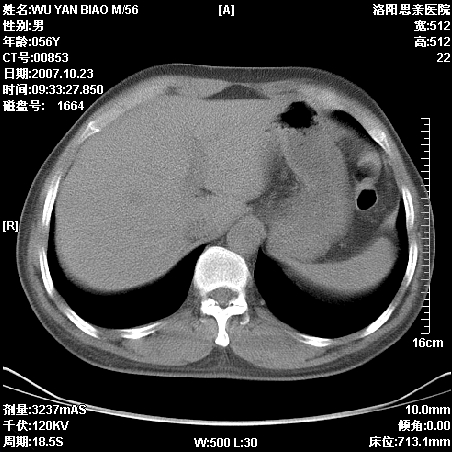

标题: CT10160:M56Y,体检发现,病人无不适,病人随访中 [打印本页]

标题: CT10160:M56Y,体检发现,病人无不适,病人随访中

后上纵隔占位,与肺交界清,宽基底附着脊柱,密度均匀,局部骨质无明确改变.

考虑;神经源性肿瘤,---起源交感n链?,不除外肠源性囊肿.

1、病灶在后纵隔脊柱旁沟内,此处是神经原性肿瘤的好发部位

2、病灶边缘光滑整齐,更说明病灶来于纵隔,由于有胸膜的包裹所以才导致这么光滑的边缘

3、病灶内的密度均匀